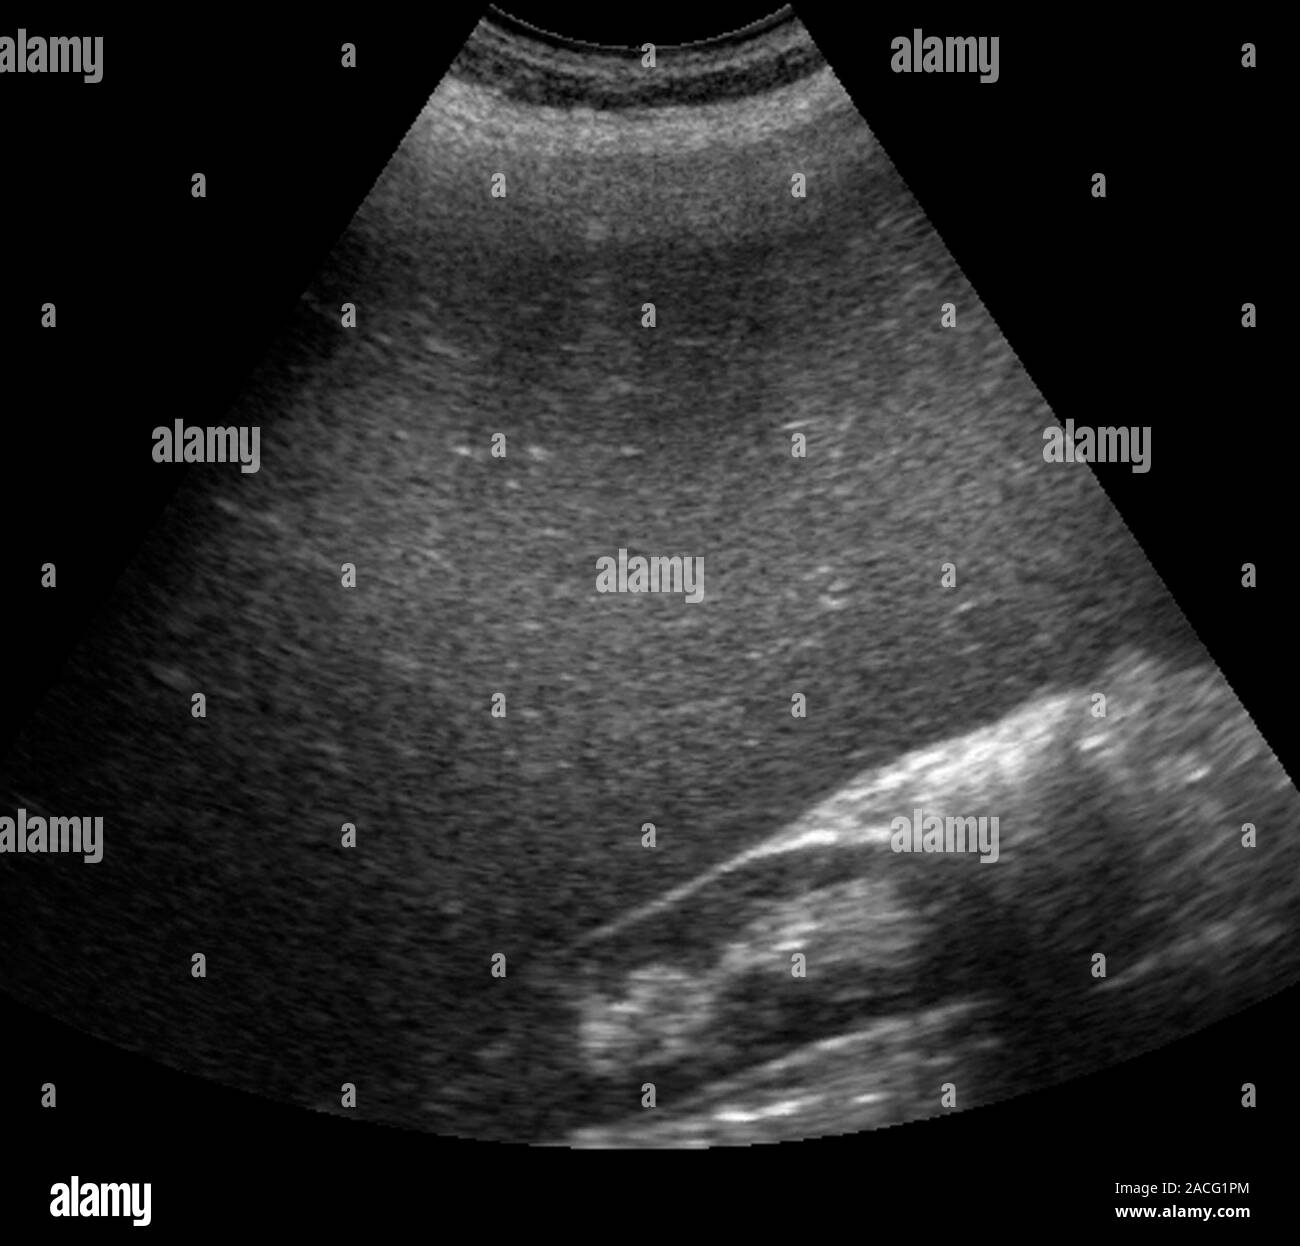

From www.alamy.com

Enlarged spleen. Ultrasound scan of an enlarged spleen (bottom right How Dangerous Is Enlarged Spleen treating the disorder that is causing the spleen to enlarge usually takes care of the problem, but sometimes the spleen must. an enlarged spleen may be up to 20 cm long and can weigh more than 1,000 g. if an enlarged spleen causes serious complications or the cause can't be identified or treated, surgery to remove. . How Dangerous Is Enlarged Spleen.